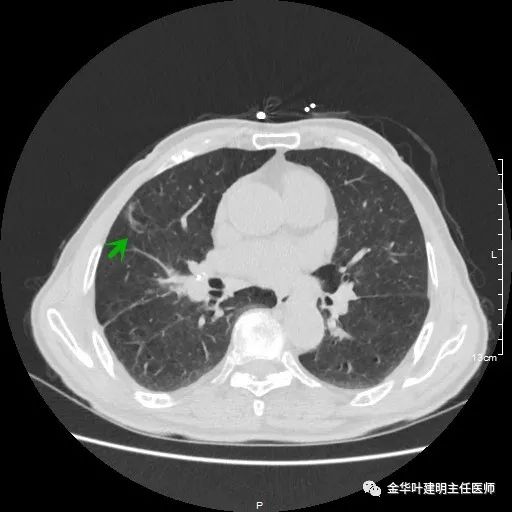

金华的某A,今年已经80岁了,前些天检查发现右下肺部占位,让我会诊。我打开电脑一看图,发现右下肺是典型的实性分叶状的占位,基本可肯定肺癌,余肺仍有多处磨玻璃影及类似慢性炎的病灶,是不是合并炎症?还是多原发肺癌?鉴于其中叶肺门部混合磨玻璃结节边缘略显模糊,为了防止炎性病灶,让其进行了10天的静脉抗炎治疗,但复查靶扫描后发现病灶无任何吸收好转,靶扫描上把细节显示的更清楚了,反而更坚定了我判断其为肺癌的结论。对于这样年纪的多原发癌,我们该如何来进行临床思考呢?治疗该如何建议与决策?当然最后的结果要如实告知患方后,由他们自己决定。

以上示右上病灶,我们称其病灶1。为囊腔型病灶,边缘为磨玻璃影,且轮廓清楚,局部有点状高密度,需考虑为囊腔型肺癌。单纯从单一病灶来看,这样的年纪可以随访或局部切除。